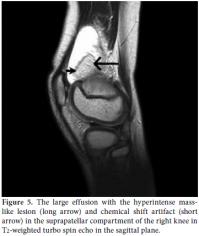

X-rays of the knees revealed minimal degenerative changes. Sonographic examination of both knees was performed by the EUB 6000 (Hitachi Medical Systems, Japan) with a high frequency linear array probe, and this revealed villous hyperechoic structures projecting into the suprapatellar effusion and a hyperechoic pseudo-mass lesion in the suprapatellar bursa in the right knee (Figure 4). Magnetic resonance imaging was performed using a 1.5 Tesla MR unit (Intera, Philips Medical Systems, the Netherlands) with an extremity coil for knee studies. The sequence included T1- and T2-weighted turbo spin echo (TSE) images in the fat-suppressed Short Tau Inversion Recovery (STIR) sequence in the axial, coronal, and sagittal planes. Magnetic resonance imaging revealed a large effusion (Figure 5), a hyperintense masslike lesion, and numerous frond-like projections in the suprapatellar compartment of the right knee (Figure 6a). The intensity of these frond-like synovial projections and the mass-like lesion, which were suppressed in the fat-saturated STIR sequences, was similar to the intensity of fat (Figure 6b). Chemical shift artifact was also detected (Figure 5). The signal intensities of these lobules were isointense with fat on the T1- and T2-weighted TSE images. These findings confirmed the fatty nature of the lesion and led us to the diagnosis of LA in the right knee. There were also mild osteochondral changes in both knees prominent in the right side. No meniscal or ligament pathology was detected in either knee.